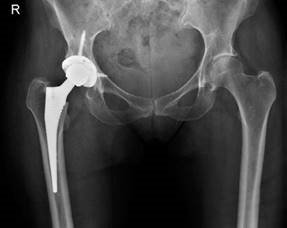

Figure 2.6 Anteroposterior (AP) radiograph of revised hip demonstrating uncemented THA with screw fixation into acetabulum. CANDIDATE : No, although a recent annotation by De Smert in the JBJS British Edition reported that two-thirds of surgeons would exclude patients of childbearing age. Most surgeons (89%) believed that women should not be excluded.4 EXAMINER : I think most hip surgeons would now avoid a resurfacing procedure in a female regardless of whether they were of childbearing age or not.5

These are her postoperative radiographs. We kept her nonweightbearing for 6 weeks as there was quite an extensive anterior wall defect in the acetabulum but she has done very well. The hip pain has settled and the abdominal mass resolved. We were very lucky as the extensive soft tissue destruction that sometimes can be seem with this condition was absent. (Figure 2.6.) EXAMINER : What are the outcomes of hip resurfacing compared with conventional THA? CANDIDATE : Several recent studies report identical Harris hip scores but a greater percentage of patients with resurfacing involved in high demand activities. There is a higher revision rate in hip resurfacing compared with conventional THA.6 EXAMINER : What factors are associated with higher revision rates for hip resurfacing procedures? CANDIDATE : These would include AVN, hip dysplasia, female sex, inflammatory arthritis, increased age, a small femoral implant and specific implant designs. Endnotes 1. Occasionally if an examiner doesn’t know what a candidate is discussing they will enquire further. Equally the examiner may let it pass so as not to reveal their own knowledge gap. Skilful, wily candidates may be able to bait and tempt the examiner into asking for clarification so as to then appear very studious and knowledgeable. Be careful however as there is a very real danger you may irritate the examiners by coming across as a ‘know it all’.